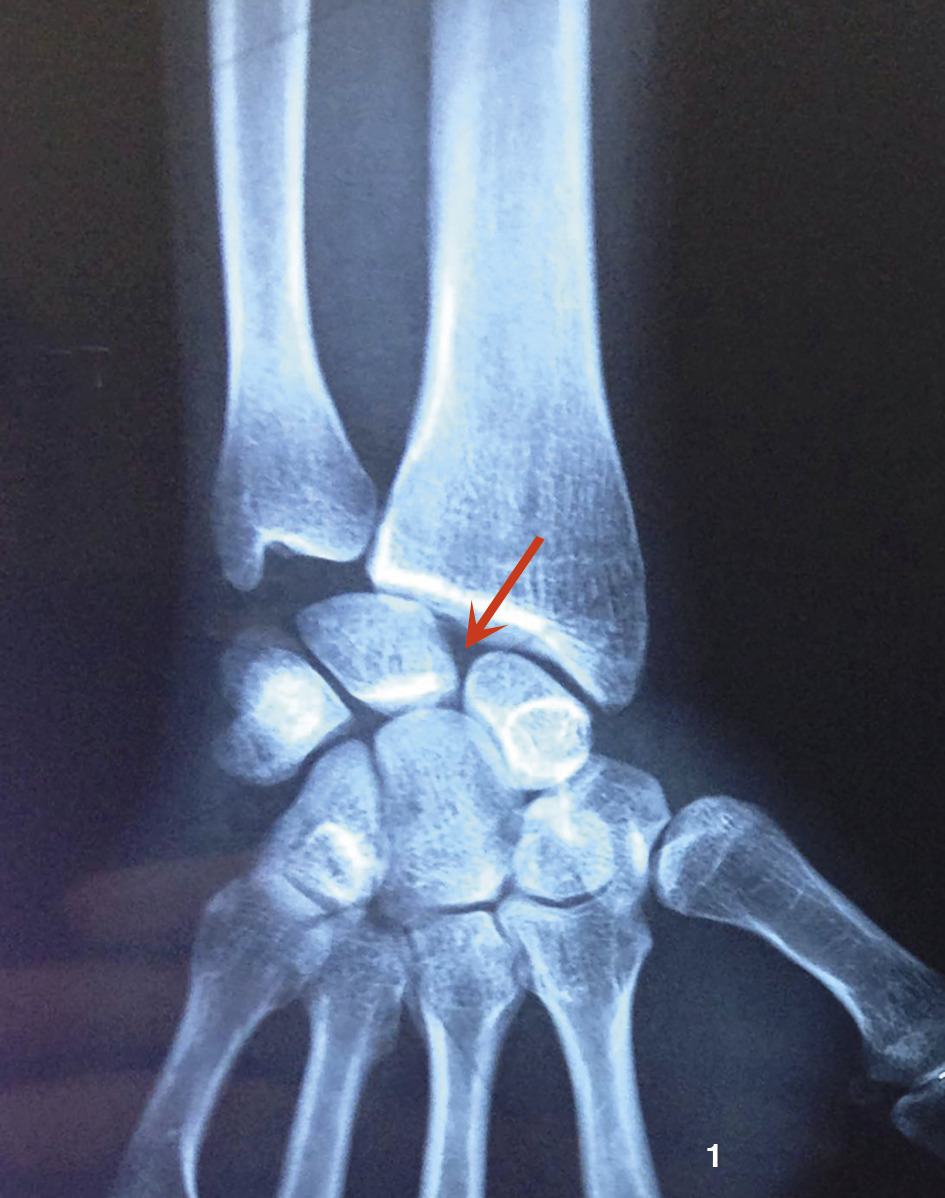

Un gendarme de 31 ans consulte pour des douleurs du poignet droit de plus en plus invalidantes. Deux mois auparavant : traumatisme en hyperextension du poignet (chute de sa hauteur) sans signe de gravité, pas de fracture sur la radio (fig. 1).

Une nouvelle série de clichés retrouve un diastasis scapholunaire.

Le ligament interosseux scapholunaire est le principal stabilisateur de l’articulation du même nom, mais c’est la rupture associée de ses segments palmaires et dorsaux qui entraîne un diastasis scapholunaire se traduisant sur les radios de face par un espace supérieur à 4 mm entre ces 2 os et une baisse de la hauteur du carpe. Sur les clichés de profil : augmentation de l’angle scapholunaire.